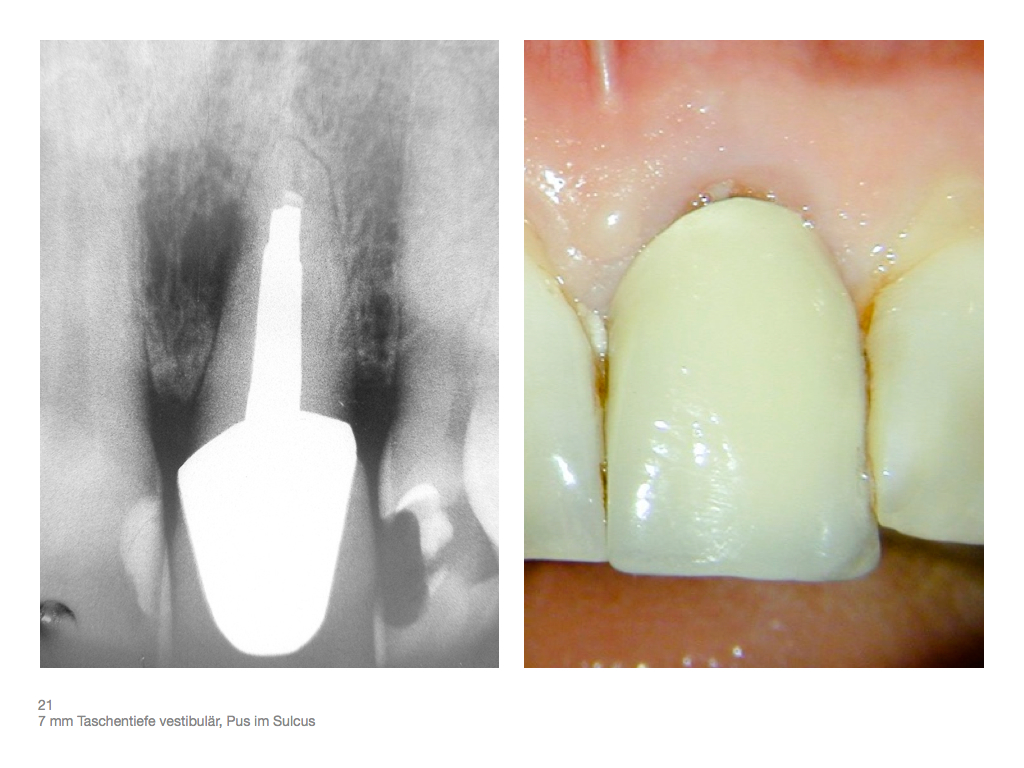

IF.004 Veröffentlicht 3. November 2012 am 1024 × 768 in Zahnerhalt „austherapierter“ Zähne durch endochirurgische Maßnahmen